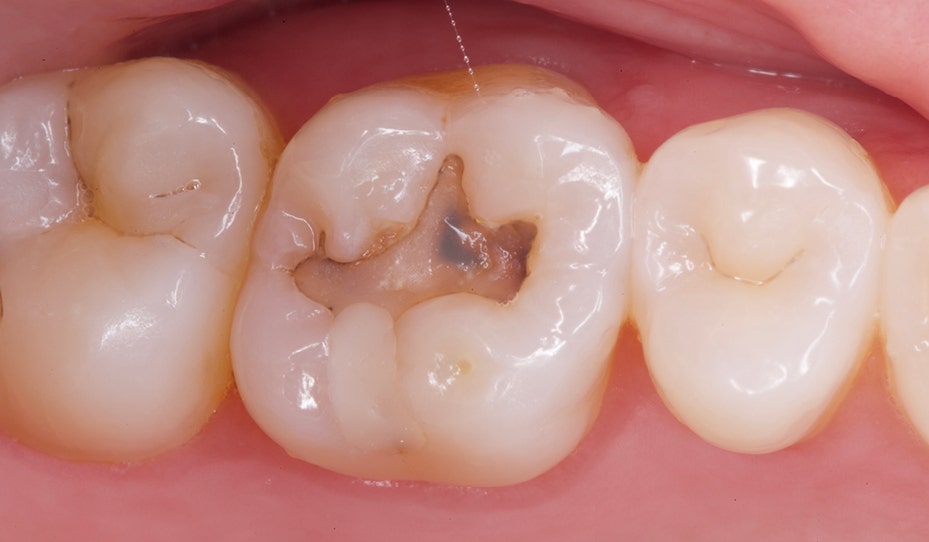

Op de foto is een molaar te zien met een duidelijke cariëslaesie die zowel glazuur als dentine heeft doorbroken, omringd door twee gezonde kiezen. Dit beeld onderstreept het belang van professioneel advies cariëspreventie om zuren uit tandplak tijdig te neutraliseren en gaatjesontwikkeling te stoppen. Een goed afgestemd gebitsverzorgingsprogramma met fluoridebehandelingen, poets- en ruittechniek vormt in de tandartspraktijk de basis van effectieve mondzorg. Regelmatige controles en mondzorgadviezen helpen de integriteit van het gebit te behouden en voorkomen ingrijpende restauraties in de esthetische tandheelkunde, zodat een sterk, gezond en stralend gebit binnen handbereik blijft.